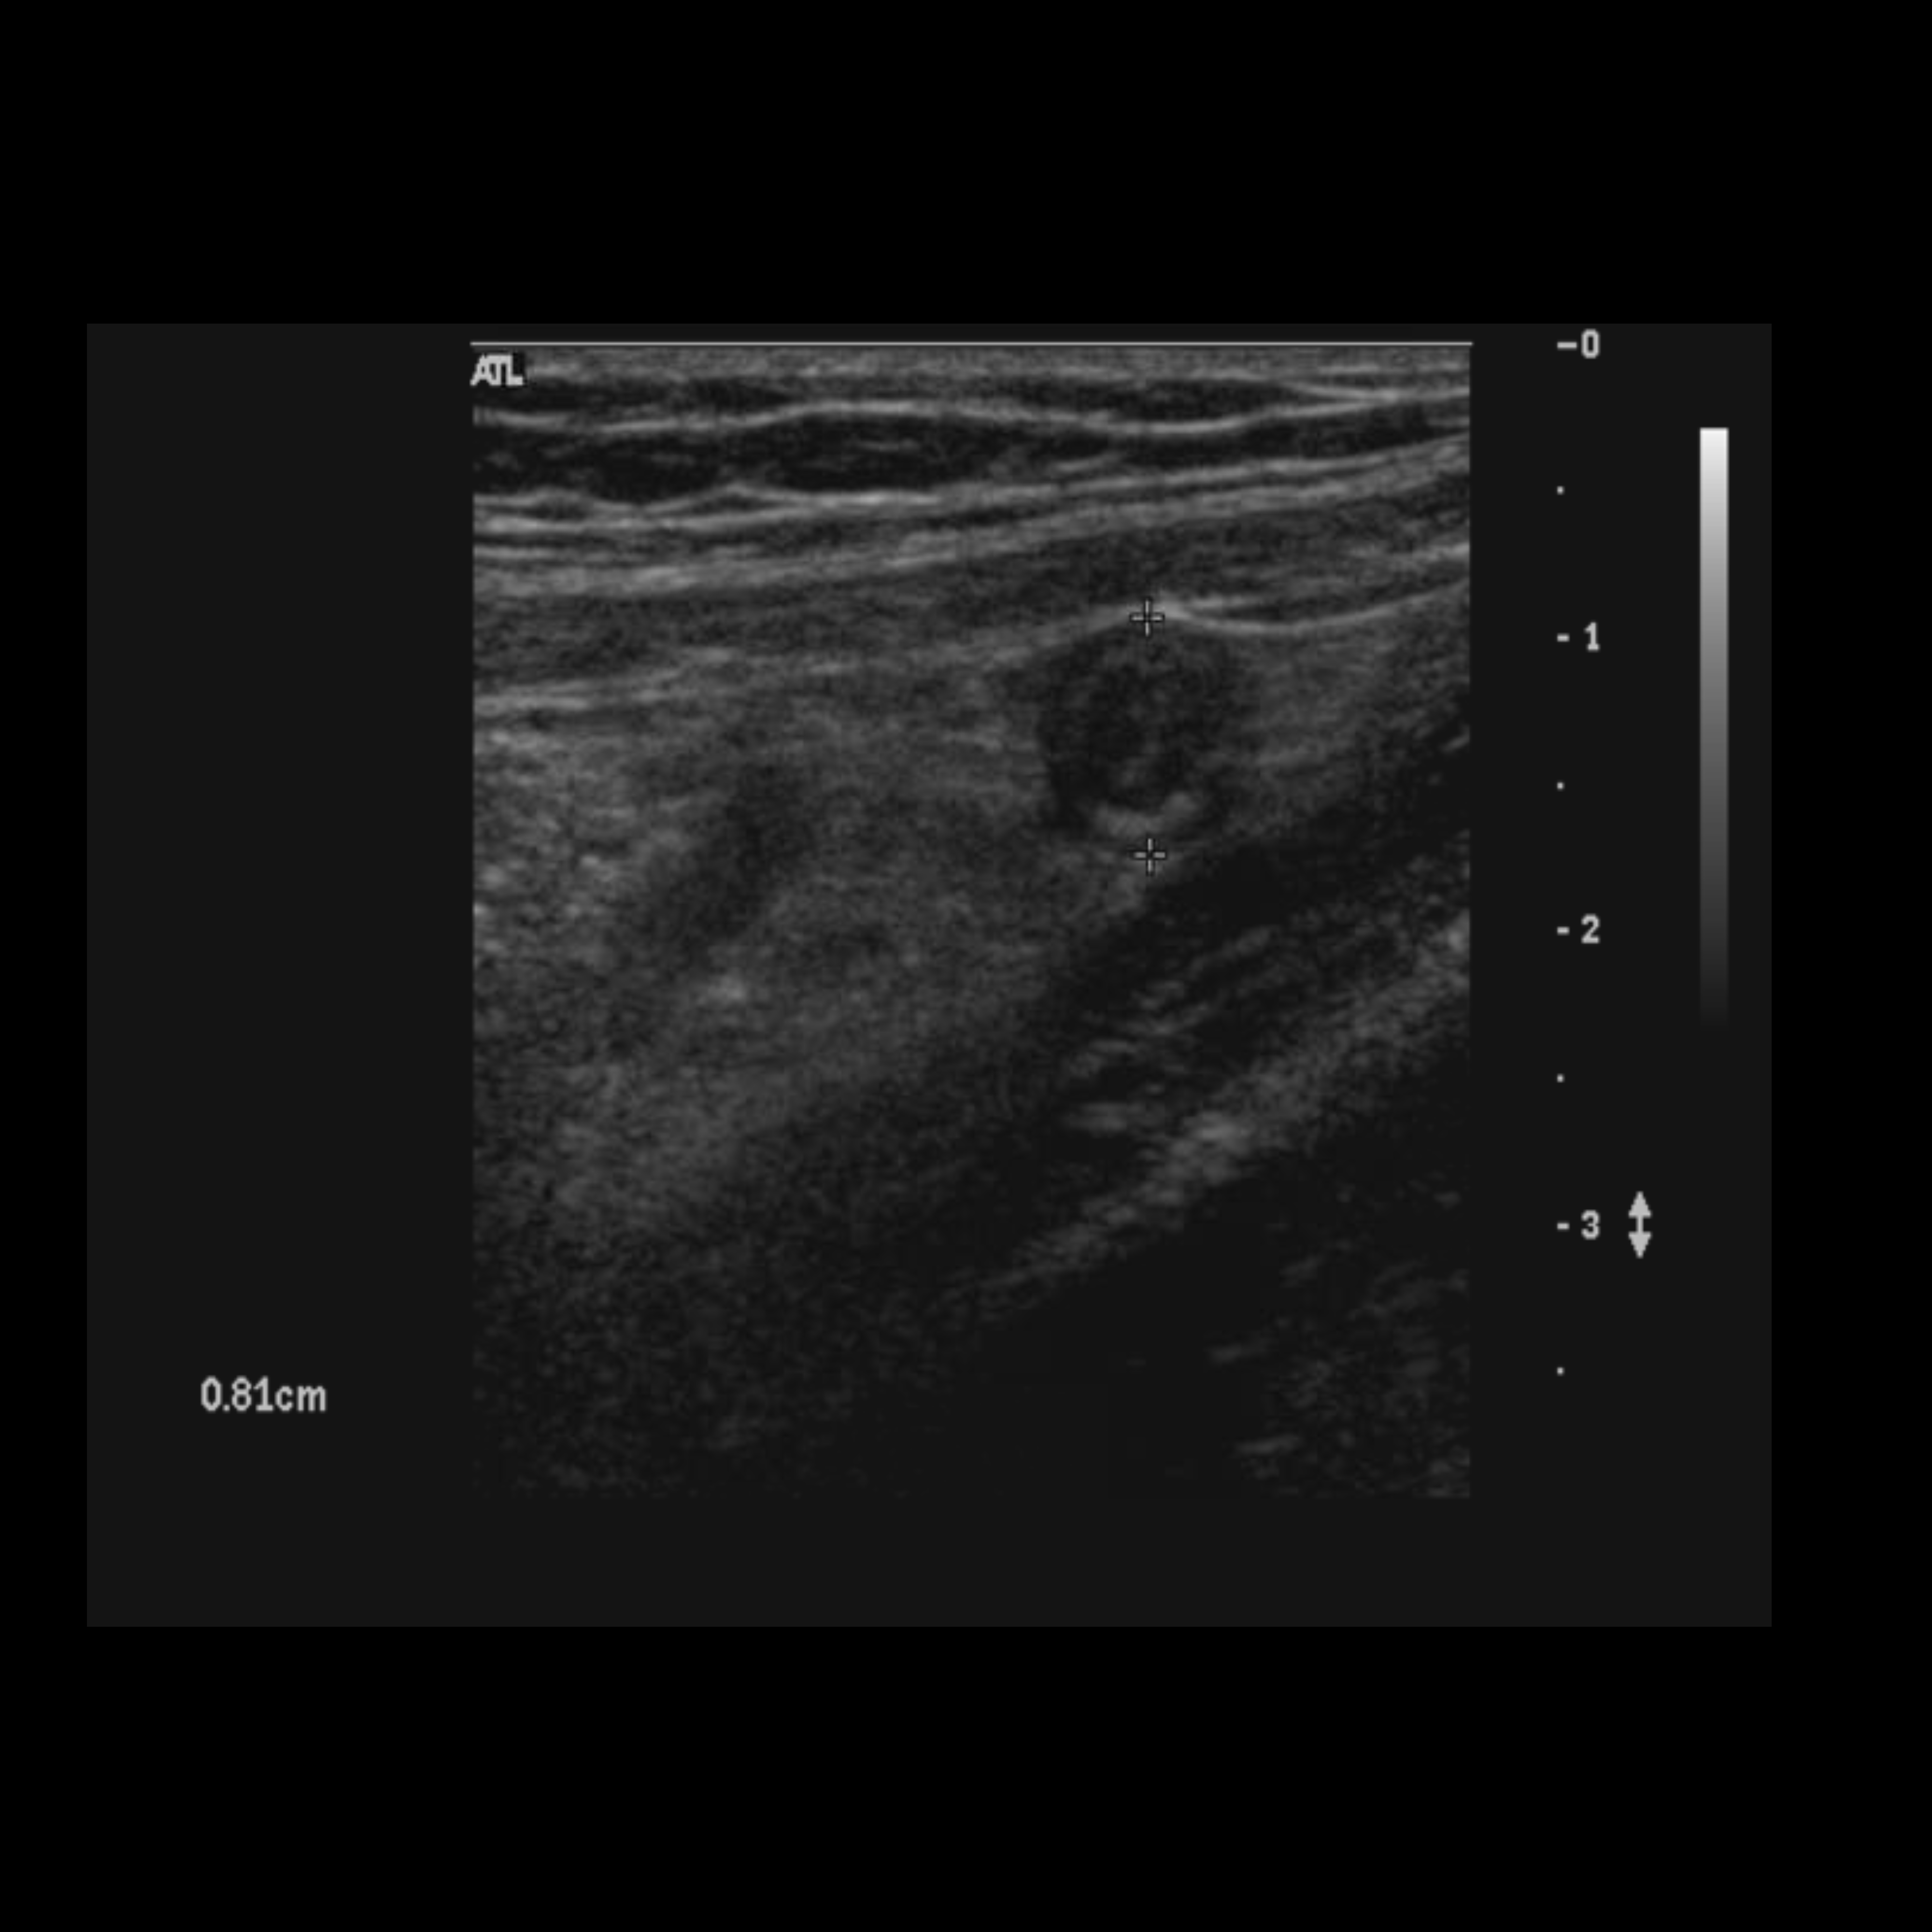

Appendicitis 12

0.9 cm positive appendicitis, with peripheral free fluid, and fat stranding.